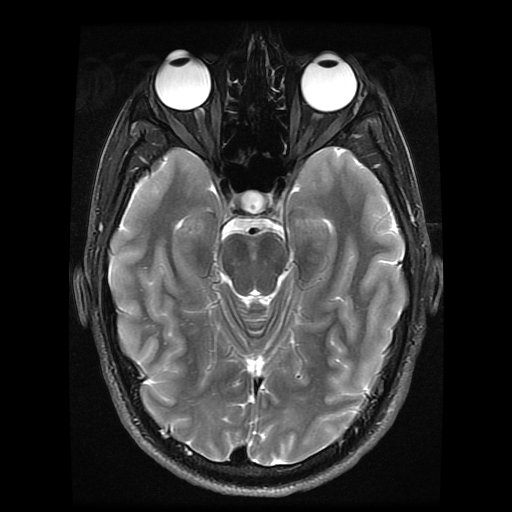

This is my favorite image btw - my eyeballs look awesome!

The immediate thing that struck me is the lack of internal structure symmetry. The folding is different between the left and the right hemisphere.

Nice work! Fascinating to observe the differences between your left and right hemispheres. Are the barrel distortions constant or a function of the scanner's travel? eg move the Z/blue line all the way to the front or back of the head, and the sides pincushion inwards. I couldn't make out if it was constant or not, but the shape of the Y/Red frame seemed to change as it moves from top to bottom.

Were you thinking about sexy women during the scan? If you focus the green axis of the scan just one click to the right from the center of your nose, your brain stem looks just like a dancer leaning against a wall.. Either that or a crucifix. Maybe you are catholic? :)